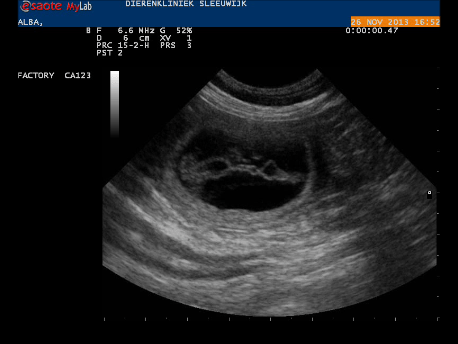

Voor zover we het niet al zeker wisten, is het nu wel zeker: Alba is drachtig!

Gisteren hebben we een echo laten maken bij Dierenkliniek Sleeuwijk. Zodra de echokop haar buik raakte, sprongen er een aantal vruchtblaasjes in beeld. Het blijft prachtig om te zien! De dierenarts heeft niet precies geteld, dat hoeft voor ons ook niet, maar het is duidelijk dat het geen klein nest zal worden. De vruchtjes zagen er goed ontwikkeld uit, en hoewel er ook in dit stadium nog van alles kan gebeuren gaan we er vanuit dat Alba over 4,5 week prachtige pupjes gaat krijgen.

Momentopname 2 (27-11-2013 15-09)